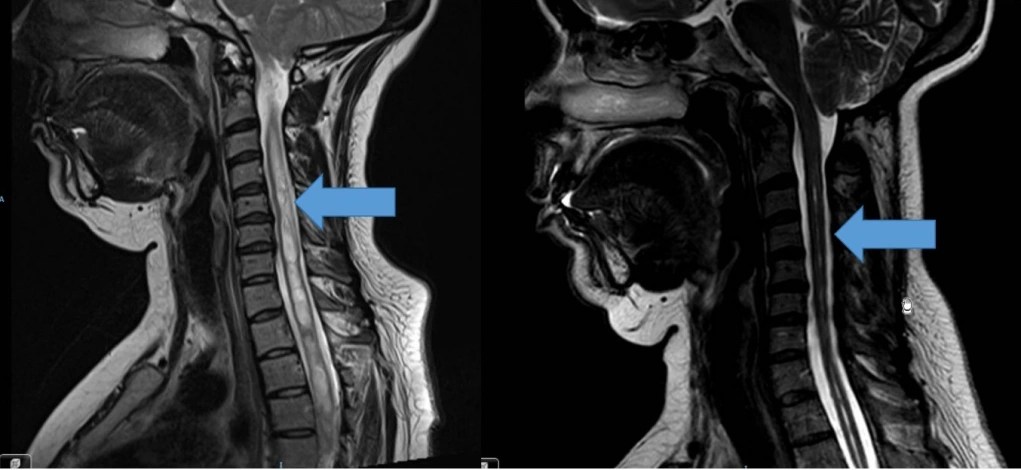

- En cuanto a los tumores que afectan a las cubiertas o elementos de sostén de las estructuras neurológicas, los más frecuentes son los meninigomas, derivados de las capas meningeas que recubren la médula espinal, asi como las schwannomas o neurinomas originados en las células de sostén de raices nerviosas. En ambos casos puede tener lugar la compresión de la médula espinal que provoque la pérdida de función de la misma con el desarrollo de una pérdida de sensibilidad y/o movilidad, asi como posible alteración del control de los esfínteres. Para su tratamiento contamos con la posibilidad de monitorización neurofisiológica intraoperatoria y Microcirugía.

- Por ultimo, lo tumores propiamente intramedulares se albergan en el interior de la médula espinal provocando además de dolor, la disfunción de la misma con la aparicion de alteraciones en la sensibilidad, esfinteres y fuerza en extremidades. Están representados fundamentalente por los astrocitomas y los ependimomas, lesiones aunque muy infrecuentes, altamente complejas precisando de tratamientos individualizados, de alta precisión y con empleo de herramientas como Microcirugía, Monitorización neurofisiológica intraoperatoria y enfoque interdisciplinar.

-Tumores espinales: Dan lugar a una gran variedad de situaciones debido a que pueden afectar a diferentes compartimentos: óseo (tumores primarios ó metástasis con o sin extensión al canal raquídeo; siendo los hemangiomas los más frecuentes), intradural-extramedular (los más frecuentes meningiomas y algunos neurinomas) e intradural-intramedular (astrocitomas y ependimomas). Suelen manifestarse con dolor, alteración de la sensibilidad y/o fuerza en las extremidades acompañada o no de alteración esfinteriana. Van a precisar cirugía en caso de que generen inestabilidad vertebral, déficit neurológico o muestren un comportamiento agresivo.